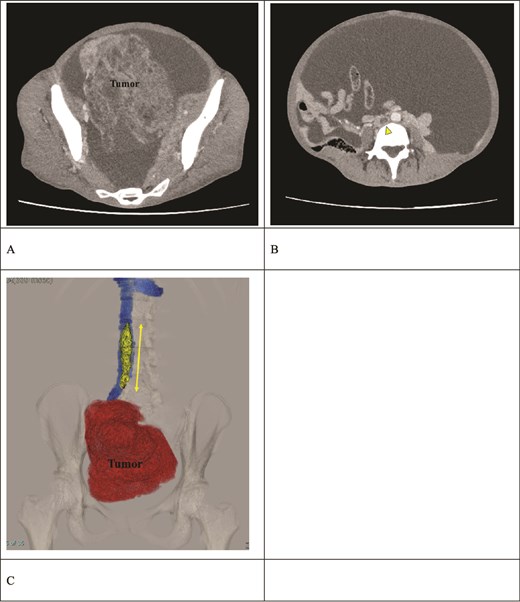

Preoperative contrast-enhanced CT. (A) A right ovarian tumor is observed in the pelvic cavity. (B) Massive ascites and a thrombus (arrow) in the IVC are observed. (C) The 3D reconstruction image shows a venous thrombus (arrow) extending from the right iliac vein to the IVC at the L2 level. The distance between the renal vein and the thrombus tip is only 25 mm.

A multidisciplinary team consisting of gynecologists, cardiovascular surgeons, and radiologists concluded that preoperative IVC filter placement was contraindicated due to the short distance of only 25 mm between the renal vein and the thrombus tip. The surgical strategy was developed to consist of simultaneous adnexal resection and thrombectomy, followed by IVC filter placement subsequent to thrombus removal. On the second day of hospitalization, the patient underwent surgery because of the high risk of PE.